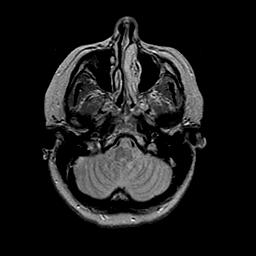

MR Study #2 -- Slice #11